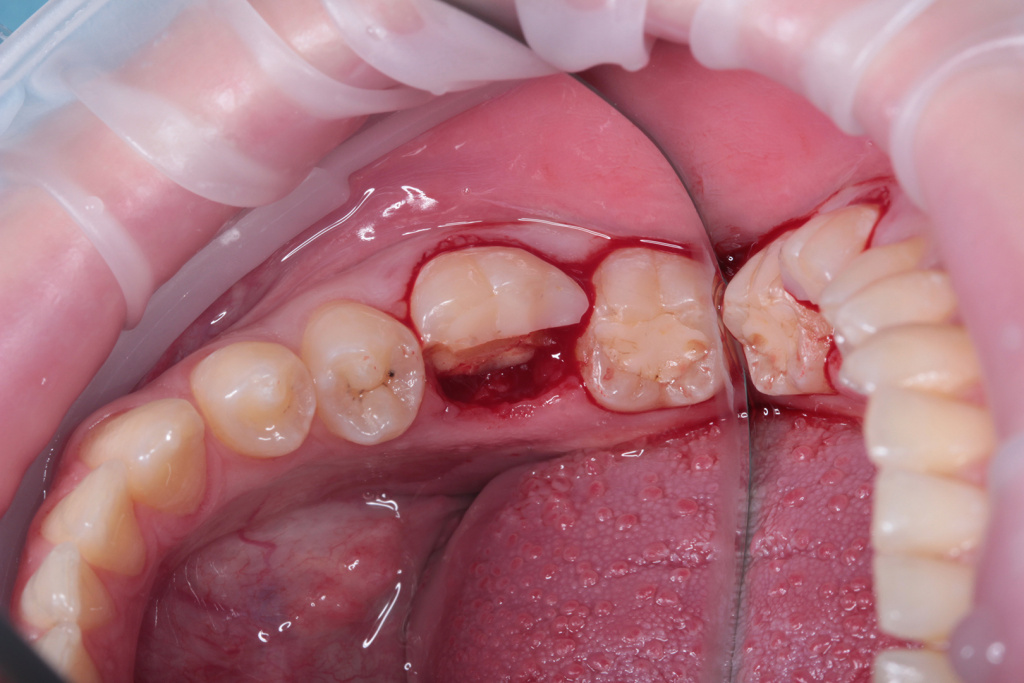

Удаление зуба 3.6

Одномоментная установка дентального имплантата, система Impro

Одноэтапная установка формирователя десны